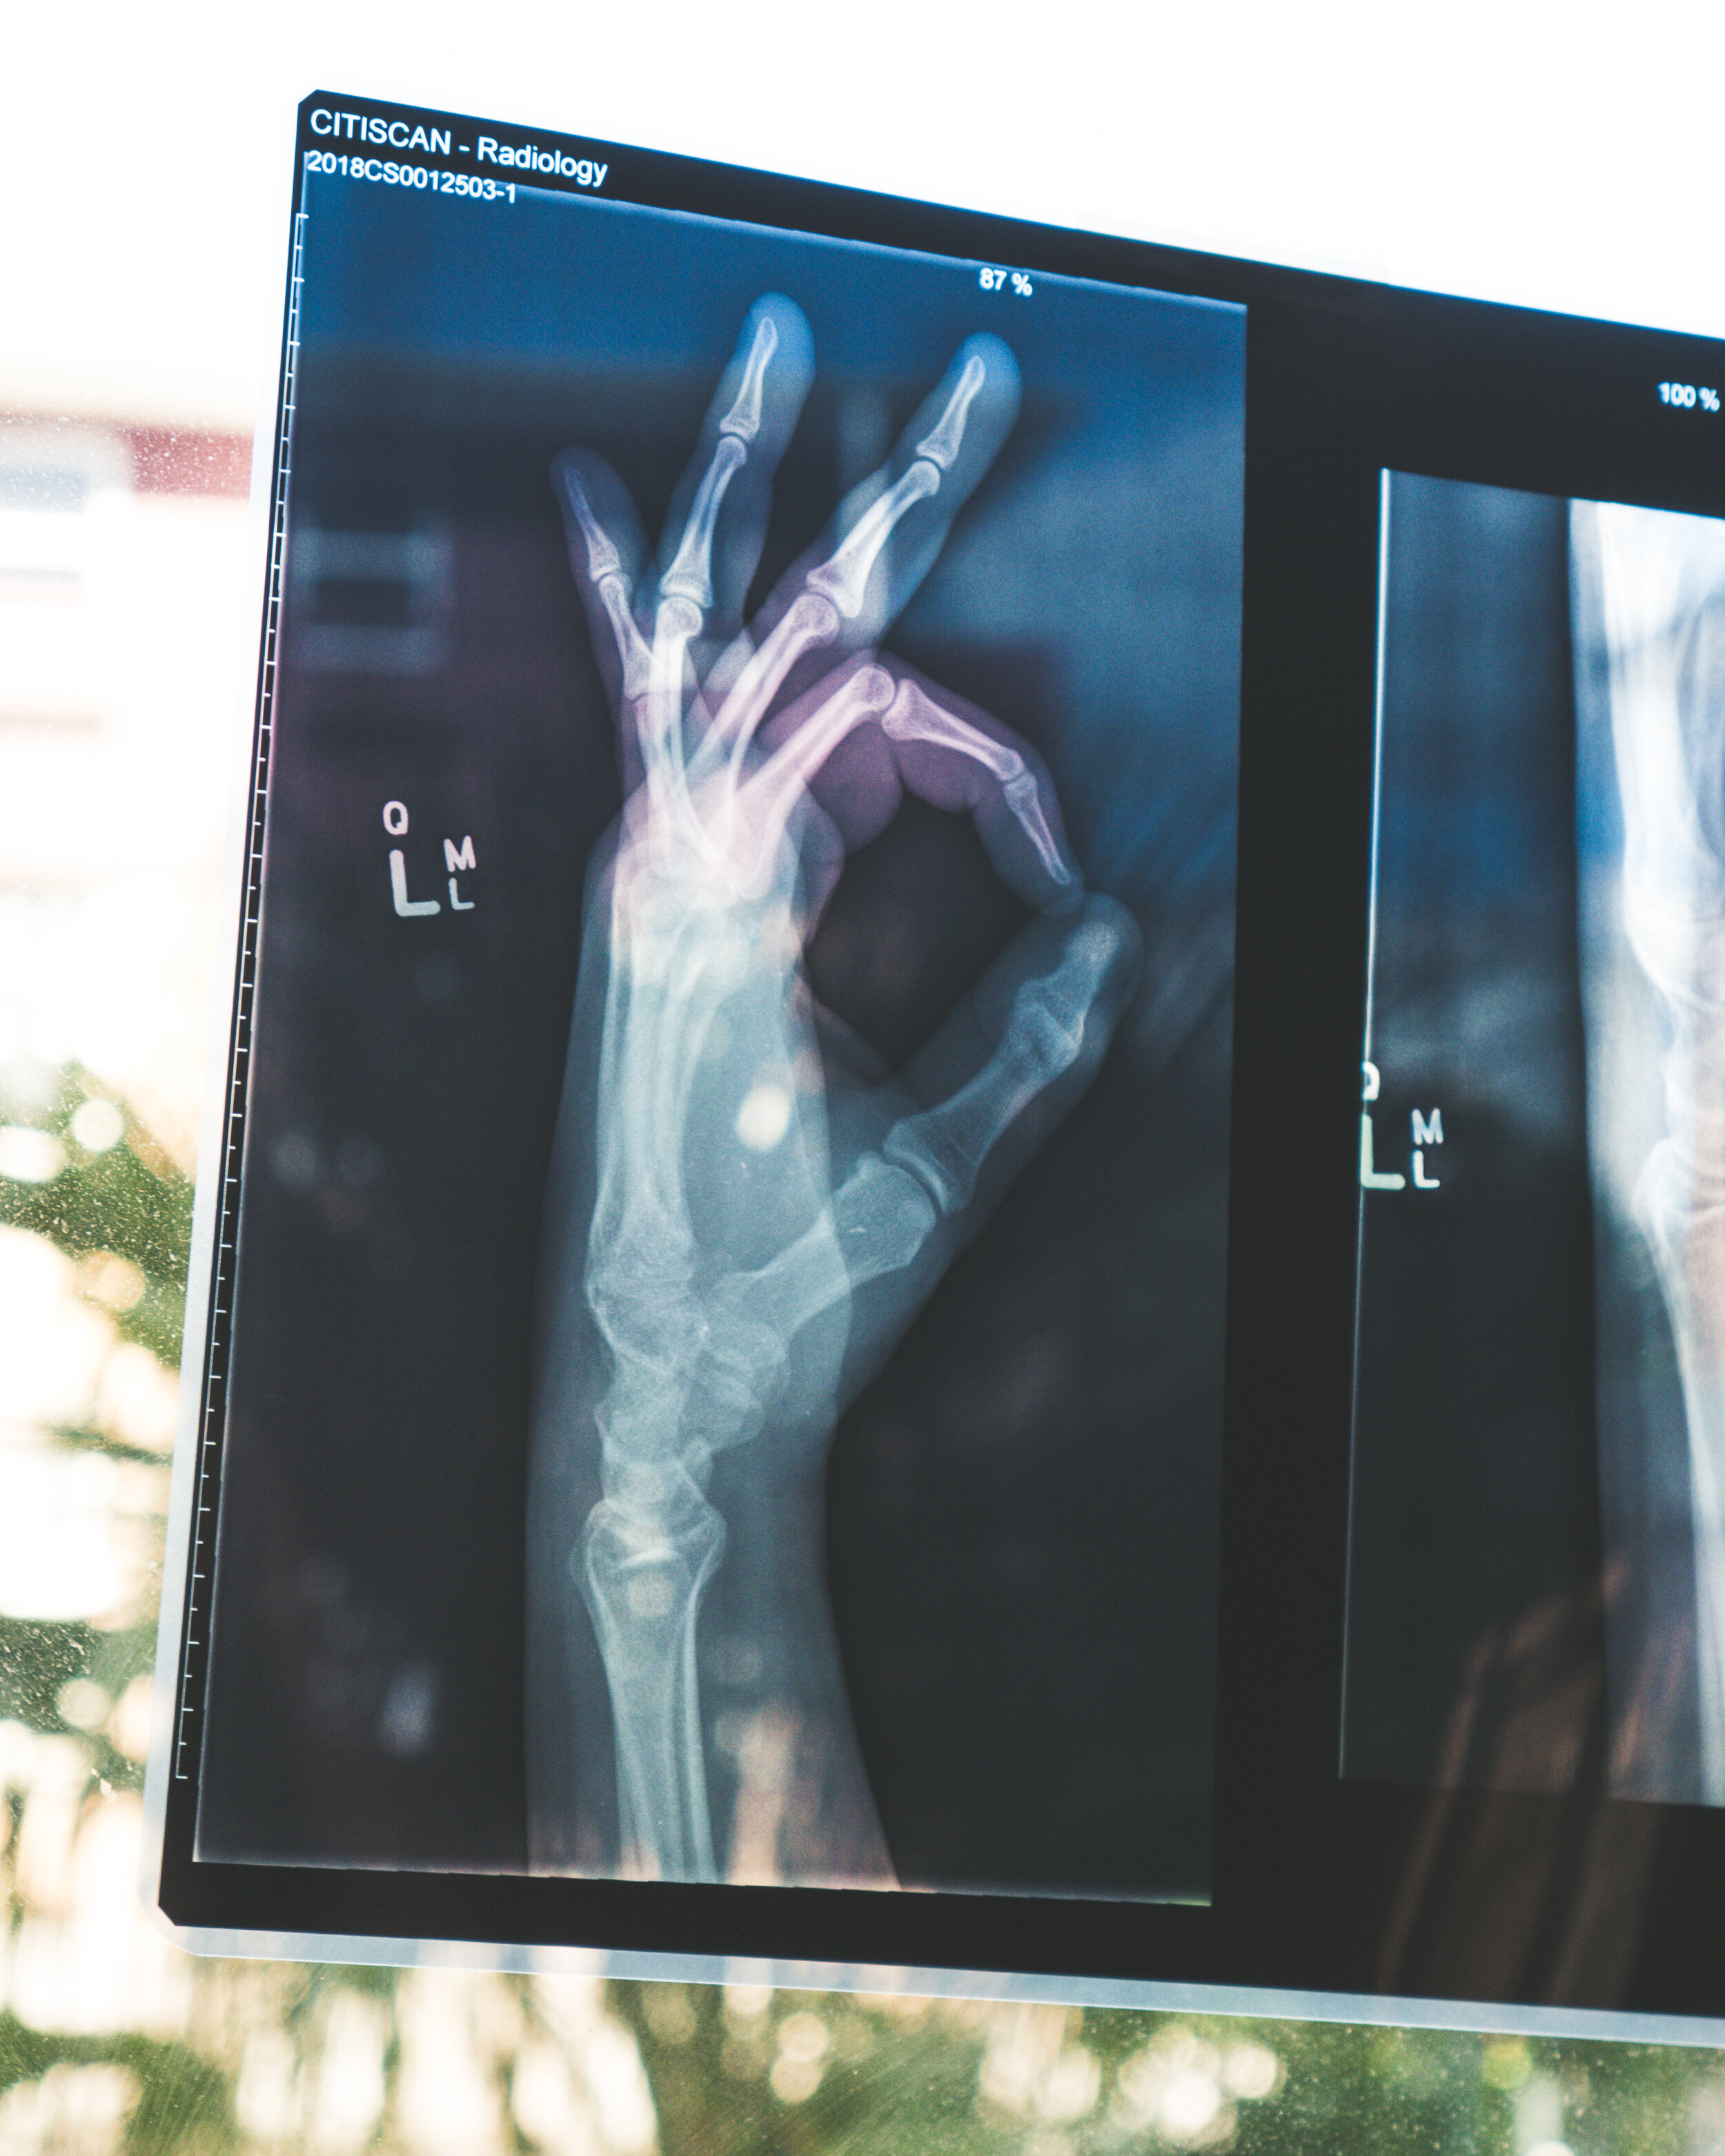

The annual celebration is an event that commemorates the discovery of the x-ray and draws attention to the important role medical imaging and radiation therapy professionals play in patient care and safety.